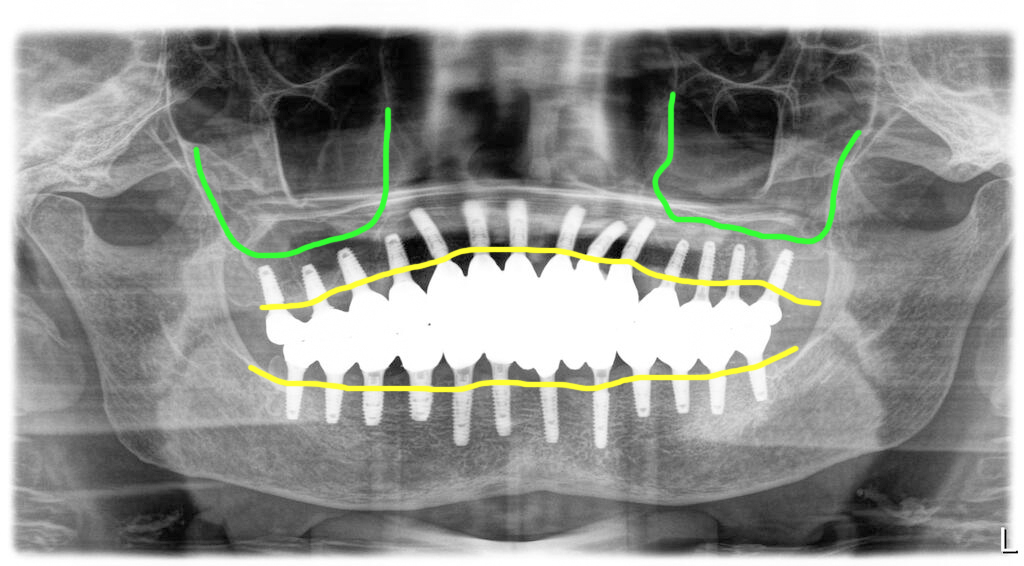

상악에 12개, 하악에 12개의 충분한 개수의 임플란트를 식립했습니다. 임시틀니 상태에서 너무 힘들었다고 했고 연령이 많아 골밀도가 떨어지는 점을 감안했어요.

조금이라도 일찍 식사를 가능하게 하려는 목적으로 충분한 개수를 심어서 수술당일부터 고정성 임시치아를 해 드렸습니다. 가벼운 식사는 가능한 상태로 만들어 드렸습니다.

1차 수술 후 6개월이 경과한 때에 먼저 심어둔 임플란트는 최종보철을 준비하고 좌측 위 어금니 부위에 추가 임플란트를 식립했습니다.

물론 기다렸다가 한꺼번에 같이 마무리를 하면 의료진은 좀 더 손쉽기는 하지만 고령인 관계로 보다 빨리 식사를 편하게 해 드리려고 먼저 골융합이 일어난 임플란트 부분을 먼저 스캔바디 스캔을 했습니다.

뼈이식 상태가 좋아 초기고정이 충분해 3개월 뒤 마무리 계획을 했어요.